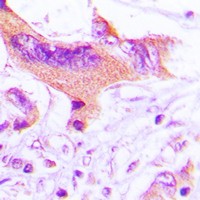

- Immunohistochemical analysis of NIP1 staining in human lung cancer formalin fixed paraffin embedded tissue section. The section was pre-treated using heat mediated antigen retrieval with sodium citrate buffer (pH 6.0). The section was then incubated with the antibody at room temperature and detected using an HRP conjugated compact polymer system. DAB was used as the chromogen. The section was then counterstained with hematoxylin and mounted with DPX.